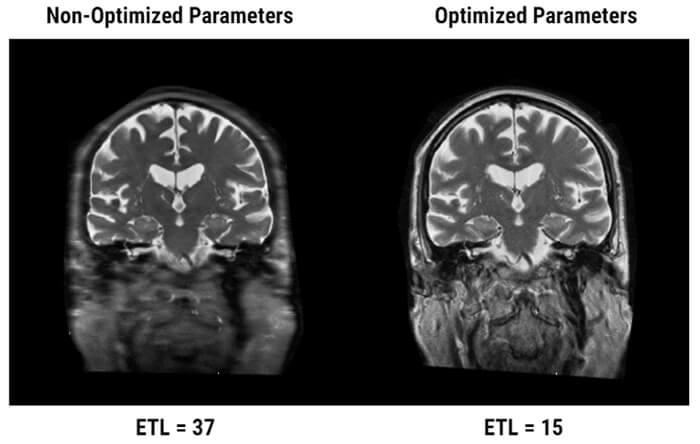

There are a few artifacts associated with multi acquisition scanning. Here we have Blurring. This artifact is characterized by an image whose spatial resolution is poor despite the small size of voxels. All the edges are blurred. While it may have the same appearance, it is important to not confuse blurring with motion artifact or a simple poor spatial resolution.

Origins:

This artifact is due to a very large difference in weight between the effective TE (TE eff) which will mark the center lines of the Fourier Transform and the weight of the last echo in the echo train or Max TE, which will mark the peripheral lines of the K-space.

When the difference between the weight of the echo that fills the center and the echoes that fill the periphery is too large, this blurring artifact appears. In an optimum setting, the Max TE should not be more than double the TE eff minus the TE min.

Optimizing the Effect:

To reduce the blurring artifact, the effective TE must be in the center of the echo train. Based on the manufacturers, the parameters are more or less automated. Some systems automatically alter the values of inter-echo space so that Max TE is double the Effective TE. Some allow full control, which implies a knowledge of this problem. Some others still leave some room for maneuver or adjustment to parameters.

Next, we will develop the rationale for a system that doesn’t have any automatic mechanism in order to properly identify the different aspects of managing these parameters